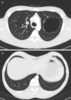

Congenital pulmonary airway malformation (CPAM), formerly known as congenital cystic adenomatoid malformation (CCAM), is a congenital disorder of the lung similar to bronchopulmonary sequestration. In CPAM, usually an entire lobe of lung is replaced by a non-working cystic piece of abnormal lung tissue. [Source: Wikipedia ]